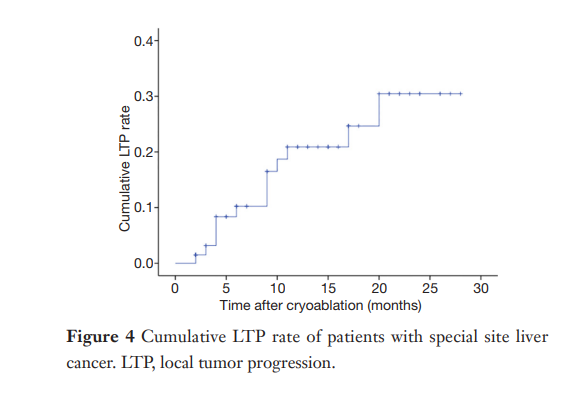

③ 总生存曲线和局部肿瘤进展曲线:冷冻消融后中位生存时间为 27.3 个月,中位局部肿瘤进展时间为 20.9 个月。

① 在我们的研究中,技术成功率为100%。动态增强MR检查随访1个月,66例患者首次技术有效率为65例(98.5%),MR影像学未发现外周脏器损伤。中位随访时间14个月(范围2-28个月)。高危部位肝癌局部肿瘤进展率曲线:6、9、15和24个月的累积局部肿瘤进展率分别为10.2%、16.5%、20.9%和30.5%。